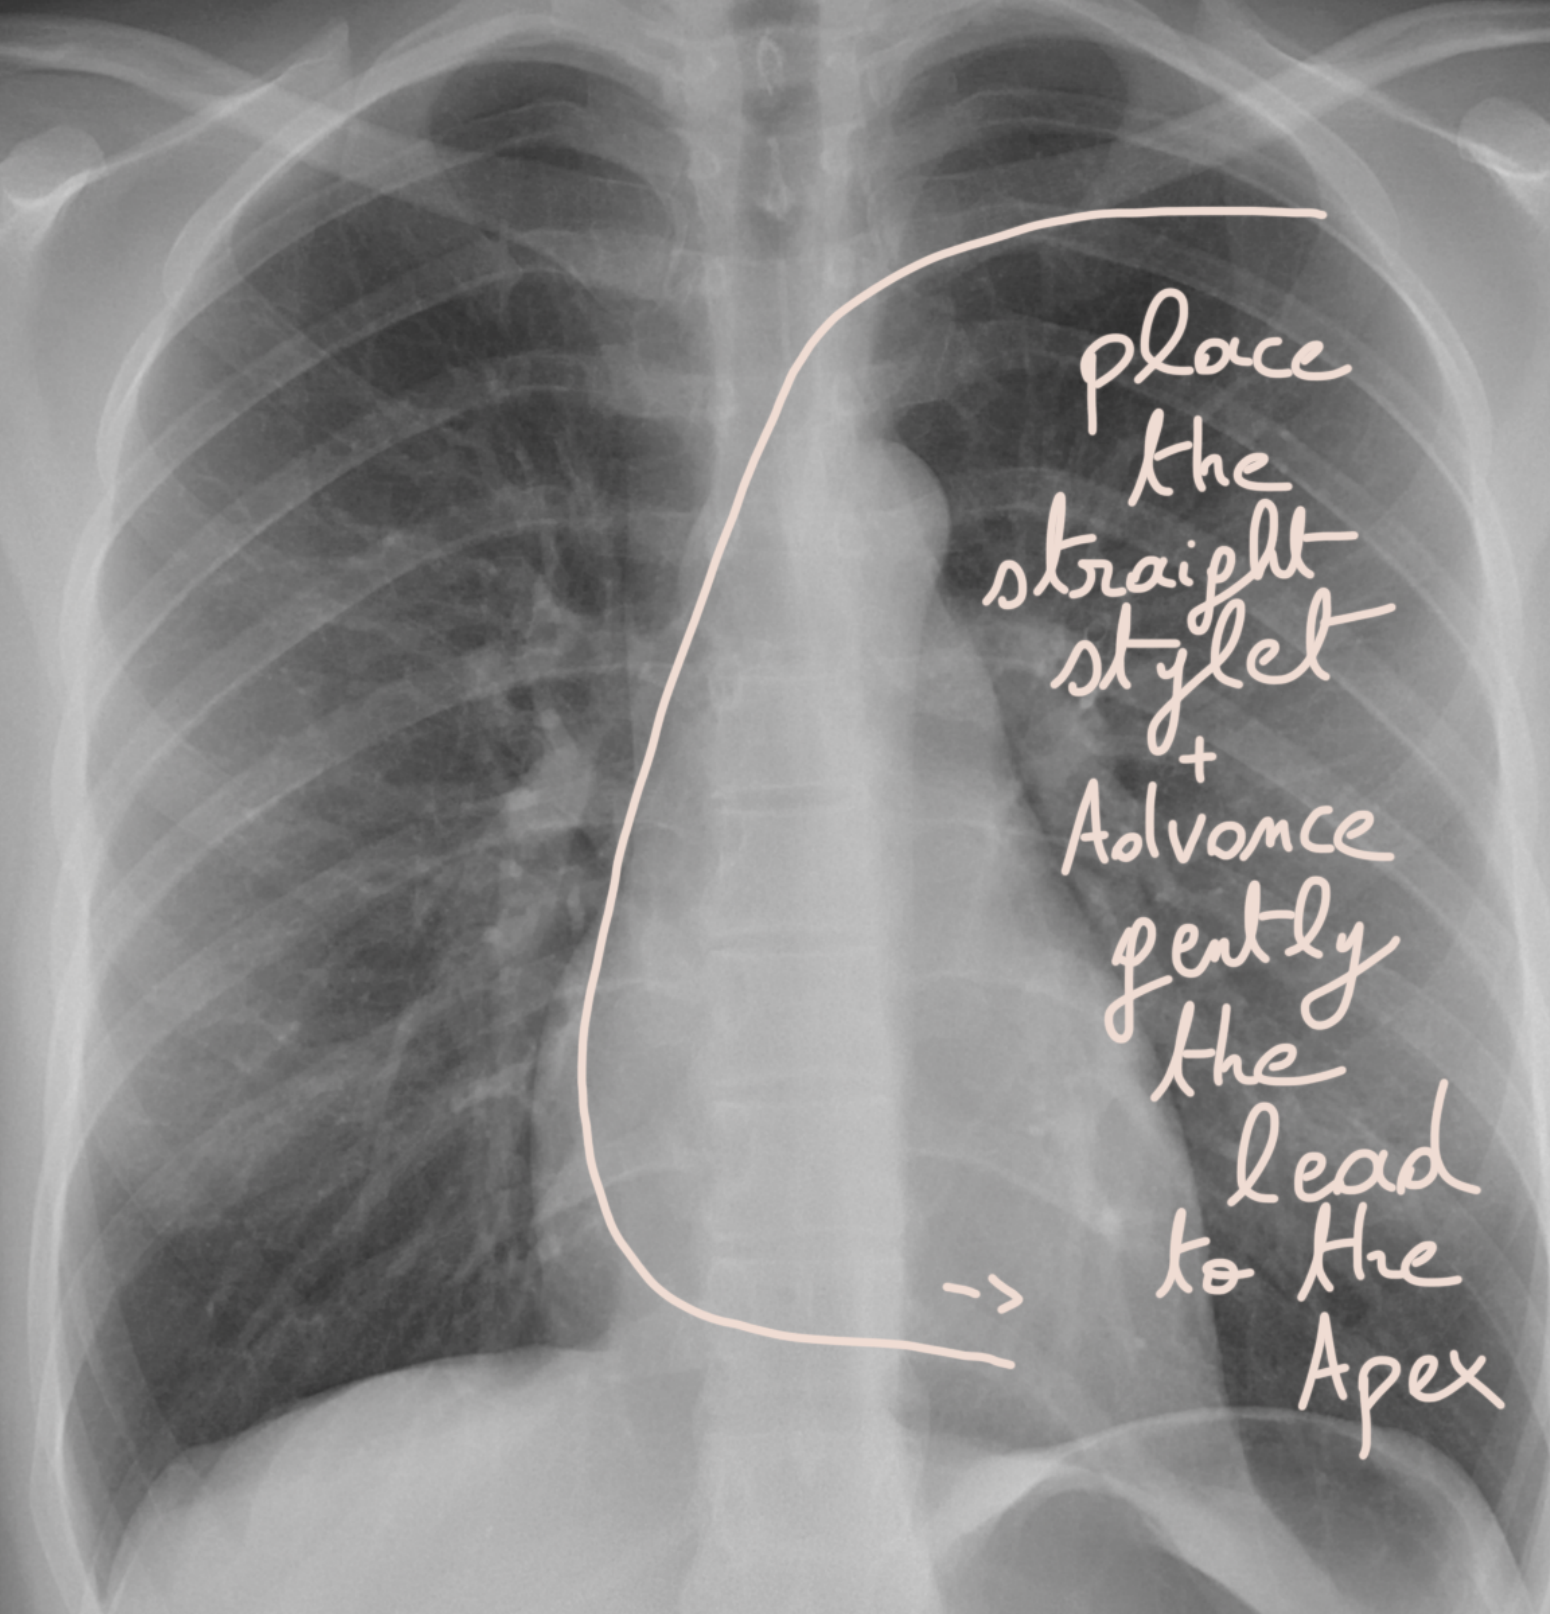

โžก๏ธ Step 17: Straighten the stylet & gently advance to the apex! ๐Ÿชก๐Ÿ“

Now, make the stylet straight and gently push the ventricular lead all the way to the apex of the ventricle.

๐Ÿšซ Do not push hard! Think of it like sliding a delicate rope into a tube ๐Ÿชข โ€” slow, smooth, and always gentle.